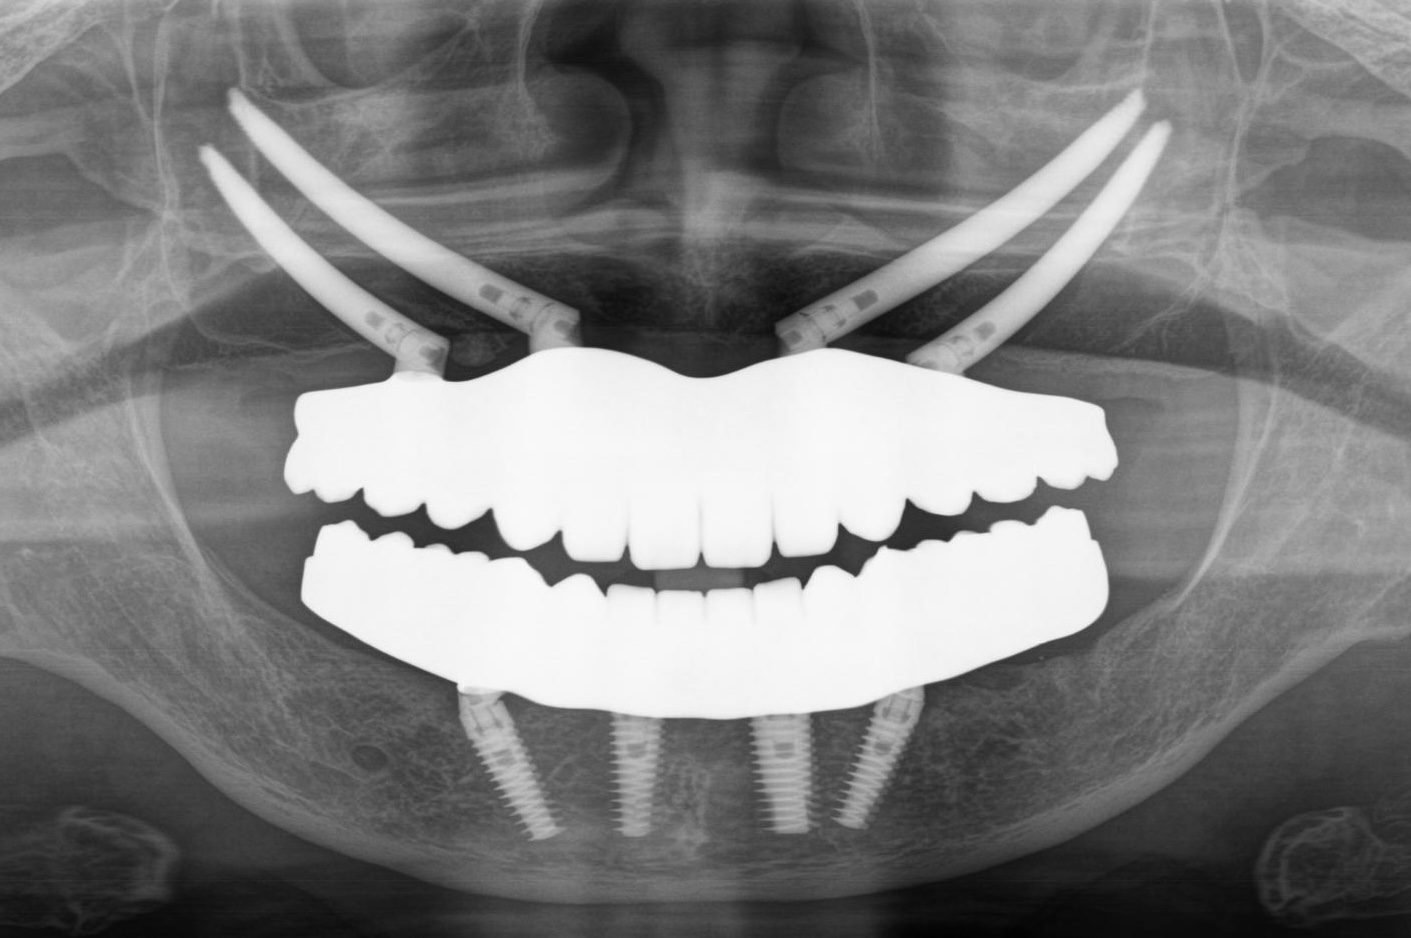

内容 :上下顎オールオン4ザイゴマ4

費用 :5,500,000円

※モニター価格

期間 :半年

リスク:出血・腫れ・痺れ・痛み